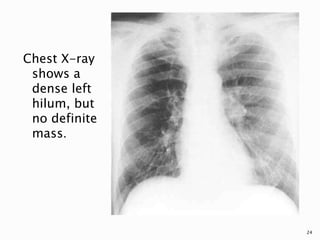

 Central tumours may be visible on the chest

density in the hilar region.

Chest X-ray

shows a

dense left

hilum, but

no definite

mass.